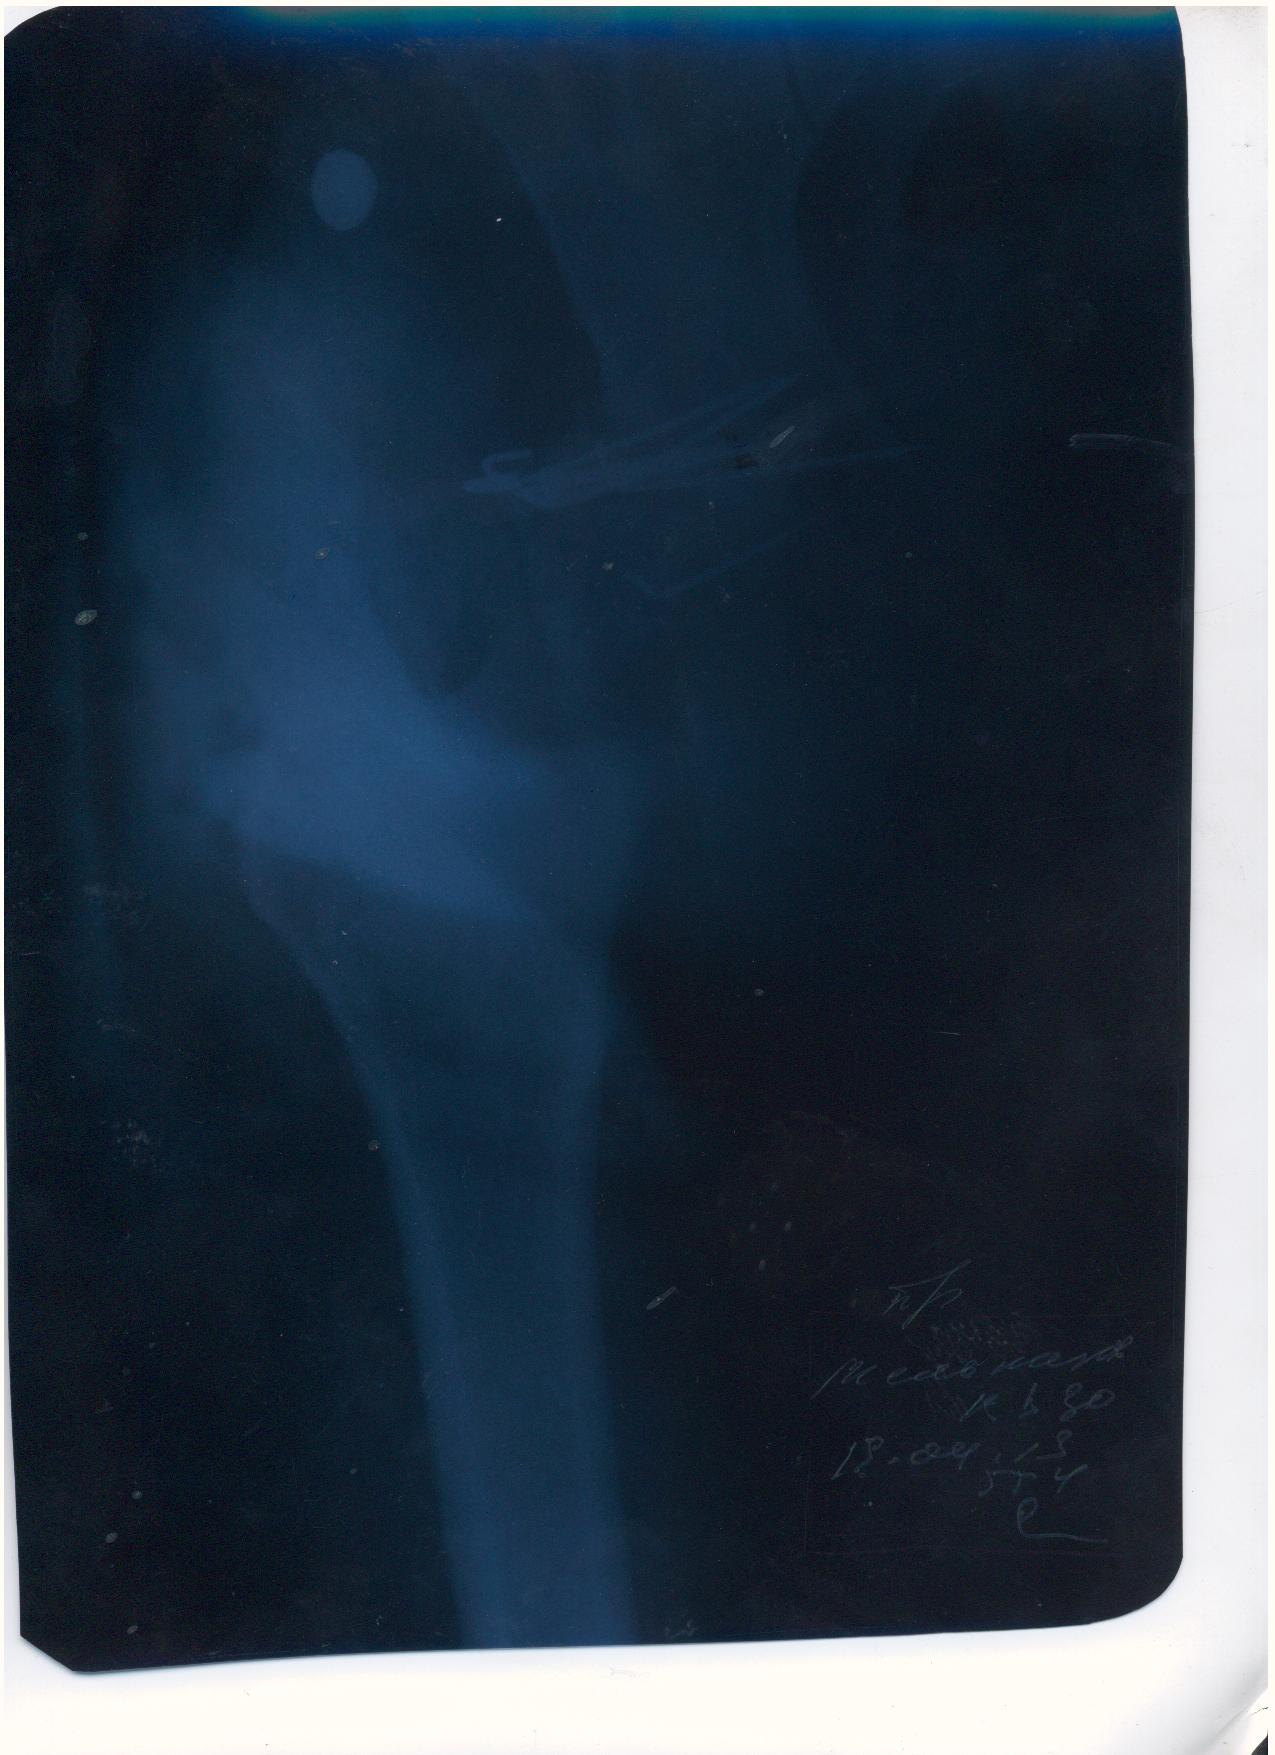

Мой товарищ попал в страшную аварию, виновник аварии как и два его пассажира погибли. Товарищ с пассажиром живы, но другу нужна сложная операция. Мы не можем никак найти врача способного прооперировать бедренный сустав, в пироговке отказали. Парню всего 30 лет всеми силами пытаемся поставить на ноги. выкладываю выписки и документы, могу выслать архивом на почту или привезти куда скажите.